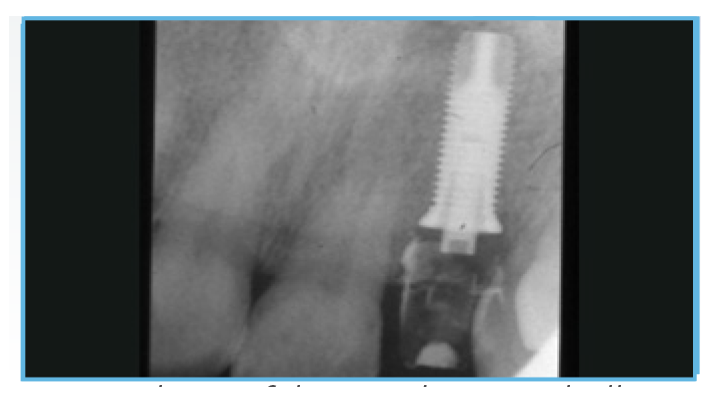

Fig. 6. A periapical radiograph was taken of the provisional restoration.